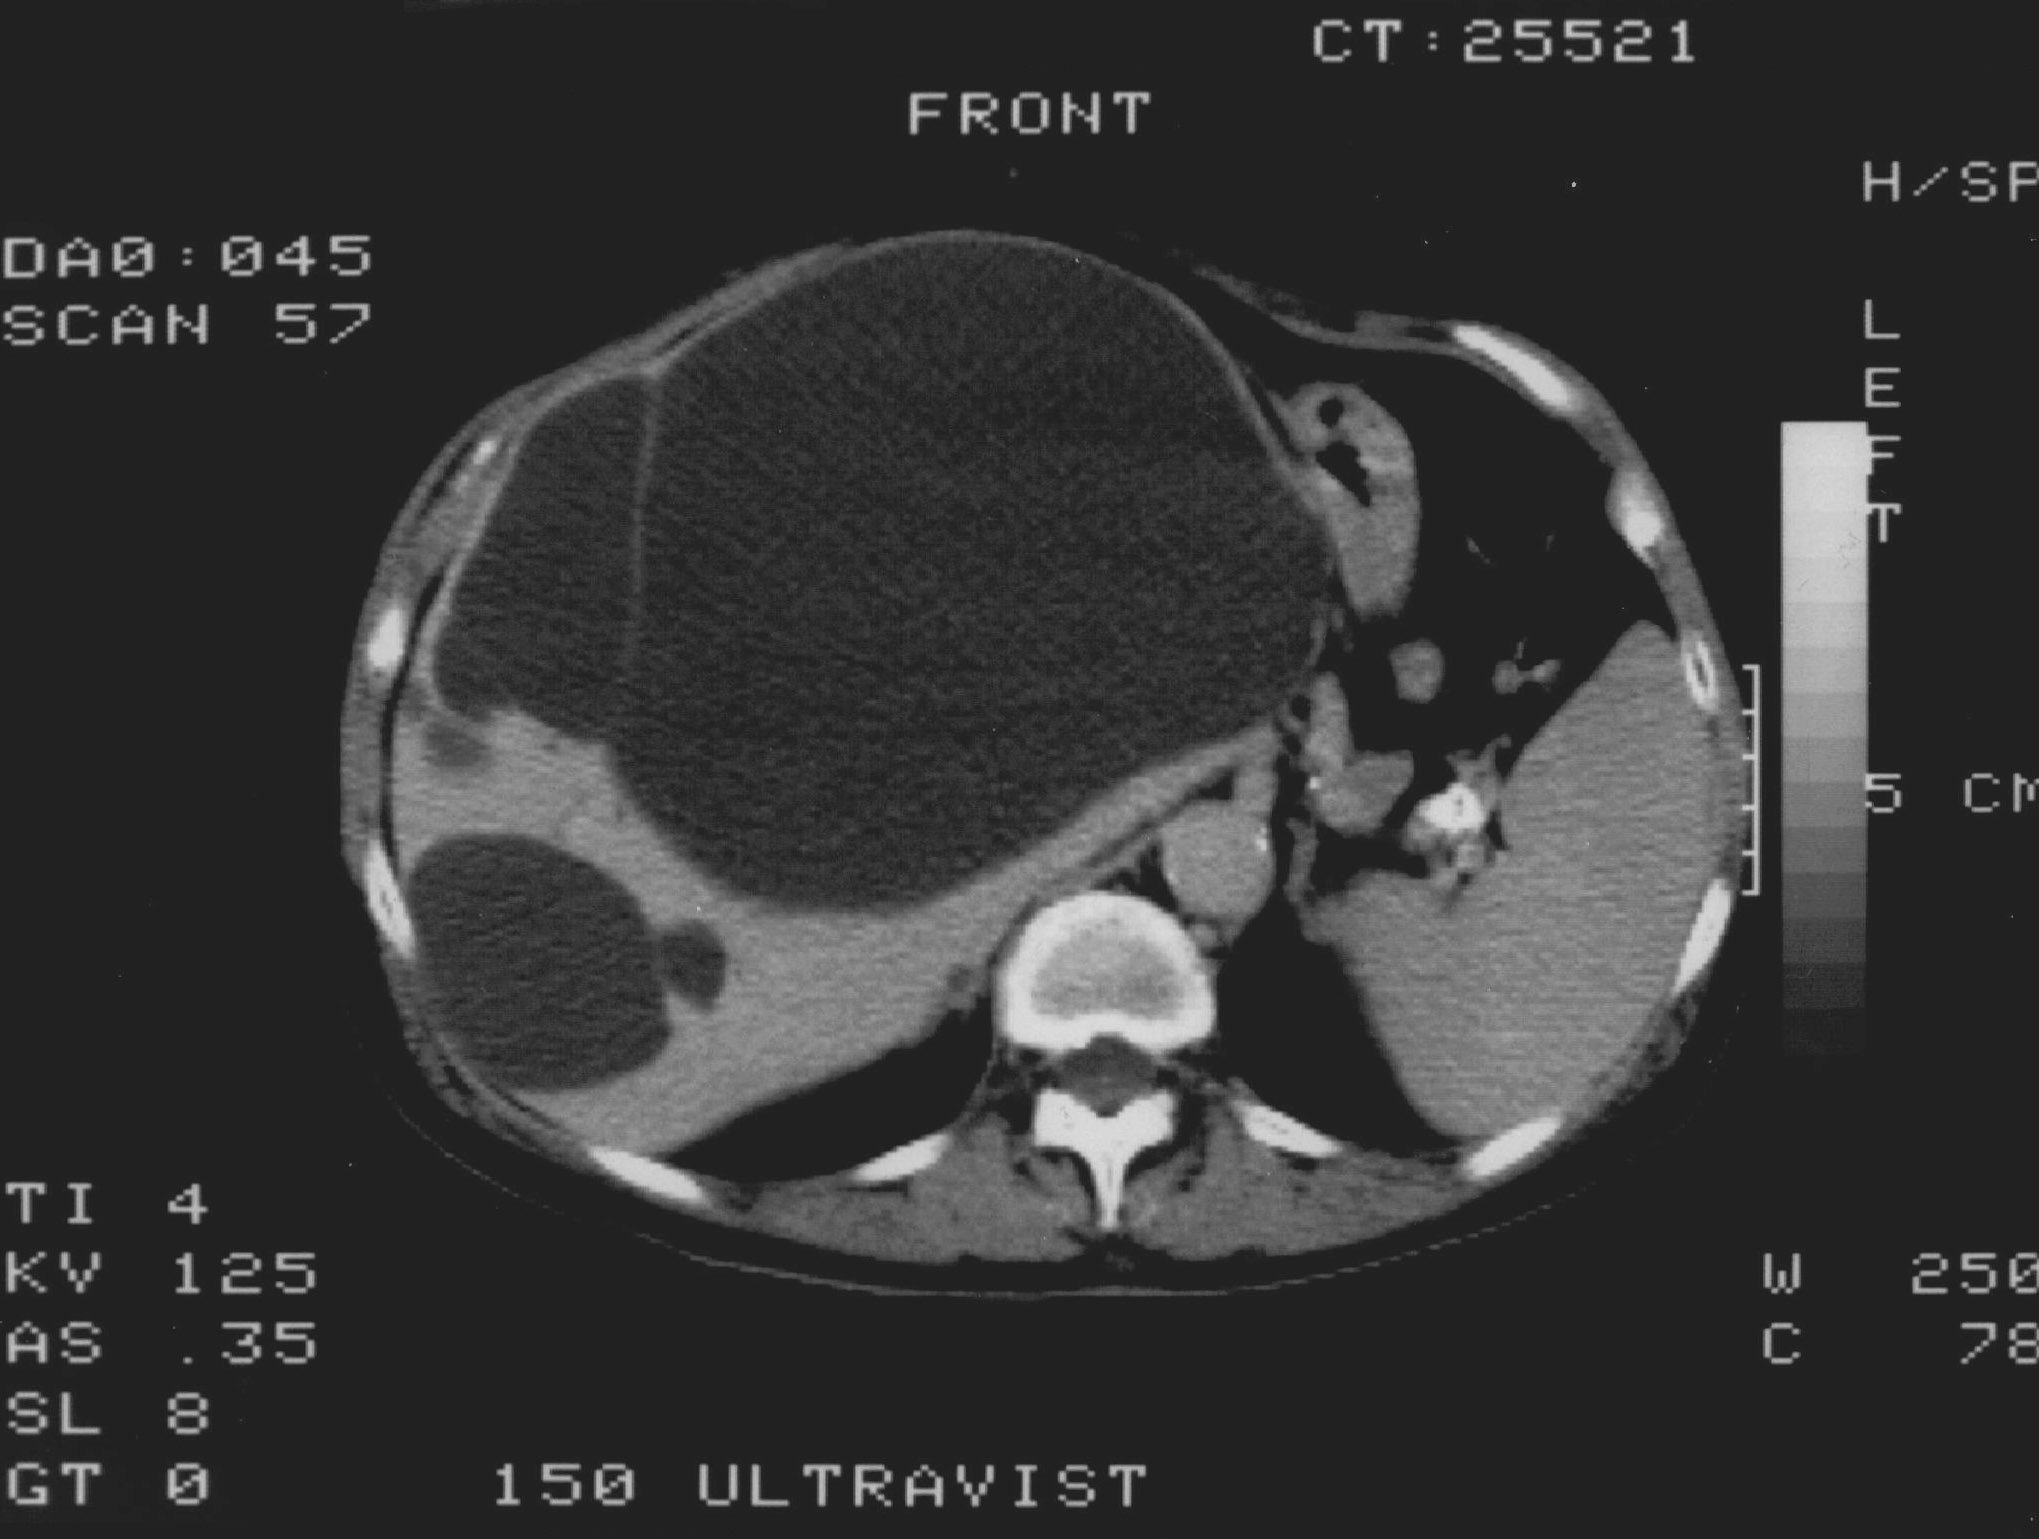

Compared to the surgical methods of past, nowadays these cystic lesions can be successfully treated percutaneously with alcoholic cyst sclerotization. (Figures 26., 27.).

Image

Figure 26. – Percutaneous ethanol cyst sclerotization ( filling up of the cyst before the sclerotization)

Figure 27. – US and CT examinations before percutaneous ethanol sclerotization (A: US examination, B: CT examination)

The puncture of the cyst is usually guided with US (rarely with CT). The puncturing needs to take place from the parenchymal side of the cyst. When its contents are removed the empty cavity is filled up with diluted contrast material to ensure that there is no contrast leakage to the surroundings. The 96% ethanol is only injected after the contrast material has been removed and no leakage was found. (The volume of the alcohol should not exceed 50-60% of the cyst or 100 ml.)

The injected ethanol is left in the cyst for 20 minutes. Following this, the alcohol is drained as well. Cystic regression is then regularly controlled with US or CT examinations. (Figures 28., 29.) Patient complaints usually cease within 4-6 weeks after the treatment.